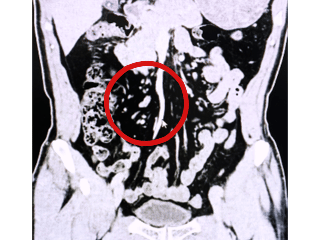

▲患者右侧双重输尿管影像

陈先生右侧的两条输尿管分别独立走行,其中一条输尿管开口位置异常,结石便隐匿在这条异常输尿管深处,这也是此前检查与手术中未能发现的根本原因。